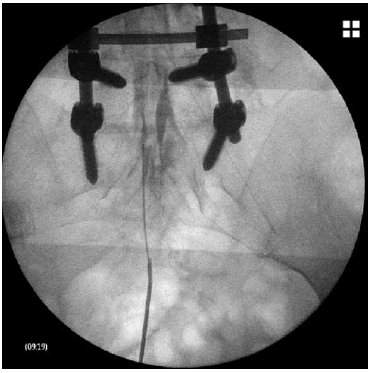

Se trata de un procedimiento que se hace con anestesia local y sedación, para la realización de una epidurolisis necesitaremos un aparato de rayos X para tener localizado el catéter en todo momento.

En primer lugar localizaremos el punto de entrada del catéter a nivel del sacro y pondremos anestesia local. Lo primero que haremos es introducir suero con una sustancia radio opaca (es una sustancia que se puede ver con rayos X), el líquido radio opaco fluye por el canal espinal, en los lugares en los que no fluye es porqué hay algo que no lo deja pasar, y es a este nivel en el que tenemos que actuar.

Posteriormente, introduciremos el catéter y con el control de visión que nos da el aparato de rayos X iremos avanzando cuidadosamente hasta el lugar de la lesión. Una vez que estemos en la lesión que queremos tratar introduciremos la medicación que consideremos más adecuada.

Imágen radiográfica epidurolisis

http://tengodolorcronico.es/site/services/epidurolisis/